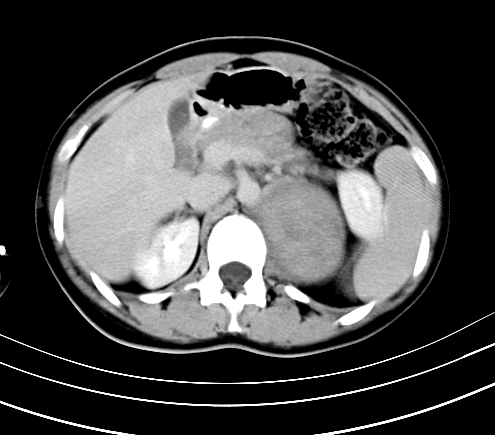

标题: CT23915:女 20岁 全身长疙瘩三年 今日多体位查 看看吧 [打印本页]

标题: CT23915:女 20岁 全身长疙瘩三年 今日多体位查 看看吧

动脉期

静脉期